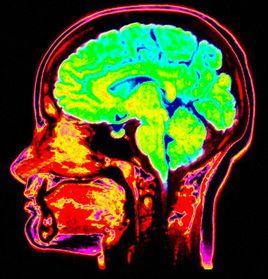

大腦掃描器科學家使用核磁共振成像和近紅外線光譜儀來監控造夢者頭部的熱量變化,從而顯示出大腦活躍性。當造夢者做夢時並未緊握手,但大腦掃描可以顯示當他們緊握真實手和夢境虛幻手時大腦活躍性特徵。